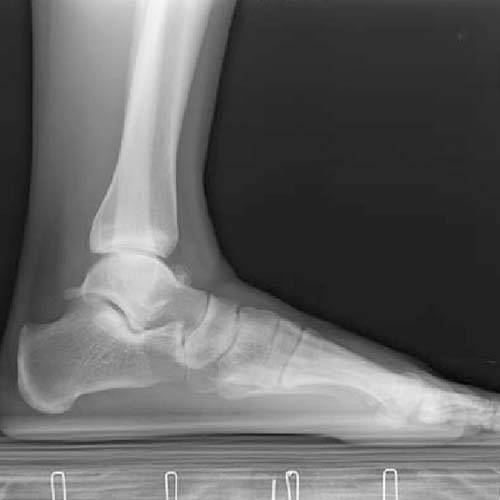

Flat feet, also referred to as flatfoot, is a condition in which one or both feet have little to no arch. When you stand, your foot pads press into the ground. In other words, it is a condition in which the entire foot from the sole to the ball of the feet touches the ground. Typically, there is no visible arch in the foot, though the arch can be seen when the foot is lifted.

A very common condition, Flat Foot or Pes Planus or fallen arches is found in about 30% of the general population. An absence or reduction of the arch, which is often found between the heel and the ball of the foot, is indicative of a flat foot. Normally, both feet are affected, but a fallen arch on only one foot is possible. A variety of conditions, including injuries, obesity, and arthritis, can result in flat feet. Flat feet can also be caused by aging, genetics, and pregnancy. You are also more likely to have flat feet if you have a neurological or muscular disease like cerebral palsy, muscular dystrophy, or spina bifida. Flat feet must be properly cared for because they can cause pain, stress, and imbalances in other parts of your body. Your entire body can be aligned by making an effort to reduce flatness. This might help with various bodily problems that flat feet can bring.

Without an arch, the entire sole touches the ground, which may cause the foot to feel stretched. Both adults and children frequently do have this illness. Flat feet don't always hurt, but they can hurt when you're doing sports.

Flat feet can be divided into two categories: flexible flat feet and rigid flat feet. When the leg is not being supported by the ground, the arch of a flexible flat foot is evident; however, when the individual is standing, the arch disappears. In a rigid flat foot, there is no arch at all.